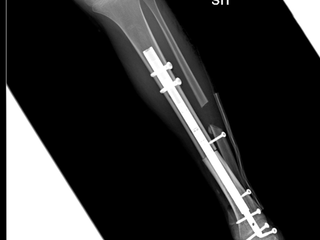

La procedura chirurgica è stata effettuata da un’équipe di ortopedici coordinata dal dottor Raimondo Piana (Chirurgia Oncologica e Ricostruttiva dell'ospedale CTO di Torino) insieme al dottor Marco Manfrini ed alla dottoressa Laura Campanacci della Clinica di Ortopedia Oncologica del Rizzoli diretta dal professor Davide Donati. La bimba, dopo la diagnosi, è stata sottoposta a chemioterapia presso il reparto di Oncoematologia pediatrica dell’ospedale Regina Margherita (diretto dalla professoressa Franca Fagioli) e nei giorni scorsi è stata sottoposta all’intervento di asportazione del tumore e salvataggio della caviglia con ricostruzione con osso omoplastico da donatore e sintesi con un chiodo allungabile, in modo da permettere la regolare crescita dell’arto senza necessità di ulteriori interventi.

La tecnica eseguita rappresenta una assoluta novità in quanto il chiodo inserito per stabilizzare l’impianto permetterà nei prossimi anni anche la regolare crescita dell’arto permettendo l’allungamento al termine della maturazione scheletrica. La chirurgia è stata pianificata nei minimi dettagli dalle due équipes di medici ed ingegneri nelle settimane precedenti. Nonostante la pandemia da Covid-19 le cure legate a questo tipo di patologie si sono svolte regolarmente e senza ritardi. La bimba ora sta bene ed è stata appena dimessa.Negli ultimi 30 anni si è vissuta la straordinaria evoluzione di nuove tecniche chirurgiche specifiche per lo scheletro infantile, riducendo drasticamente il numero di amputazioni e riuscendo ad applicare nella maggior parte dei casi un approccio conservativo - ricostruttivo, volto a migliorare il recupero funzionale e ad assicurare una migliore qualità di vita ai pazienti e alle famiglie.